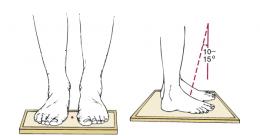

külgsuund seistes